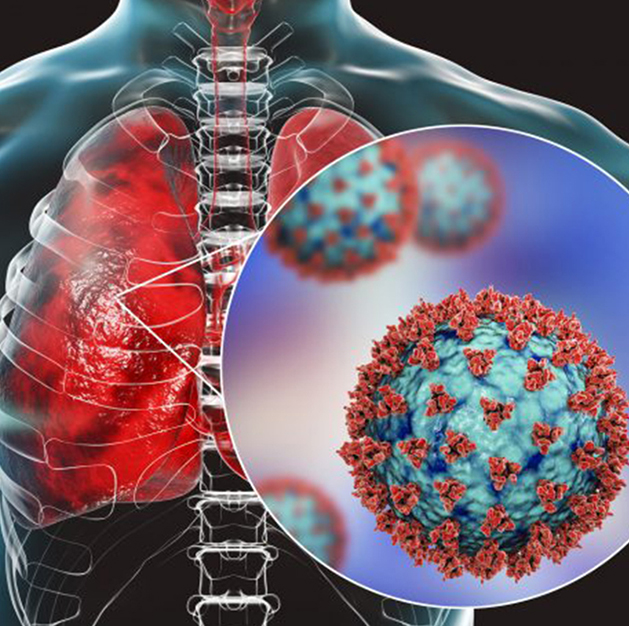

COPD & Asthma

Interstitial Lung Diseases (ILD)

Tuberculosis (TB)

Respiratory Infections & ARDS